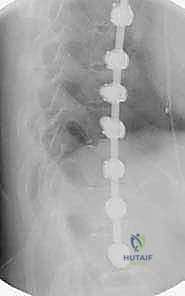

2. التصوير بالأشعة السينية (X-Rays)

هو المعيار الذهبي لتشخيص الجنف. يتم التقاط صور شعاعية لكامل العمود الفقري (من الرقبة إلى الحوض) من الأمام والخلف والجانب، والمريض في وضع الوقوف. من خلال هذه الصور، يقوم الدكتور هطيف بـ:

* قياس زاوية كوب (Cobb Angle): وهي الزاوية التي تحدد شدة الانحناء. الانحناءات الأكبر من 10 درجات تُعتبر جنفاً.

* تقييم النضج العظمي (Risser Sign): من خلال فحص عظام الحوض لمعرفة ما إذا كان المريض لا يزال ينمو، مما يساعد في التنبؤ باحتمالية تدهور الانحناء.